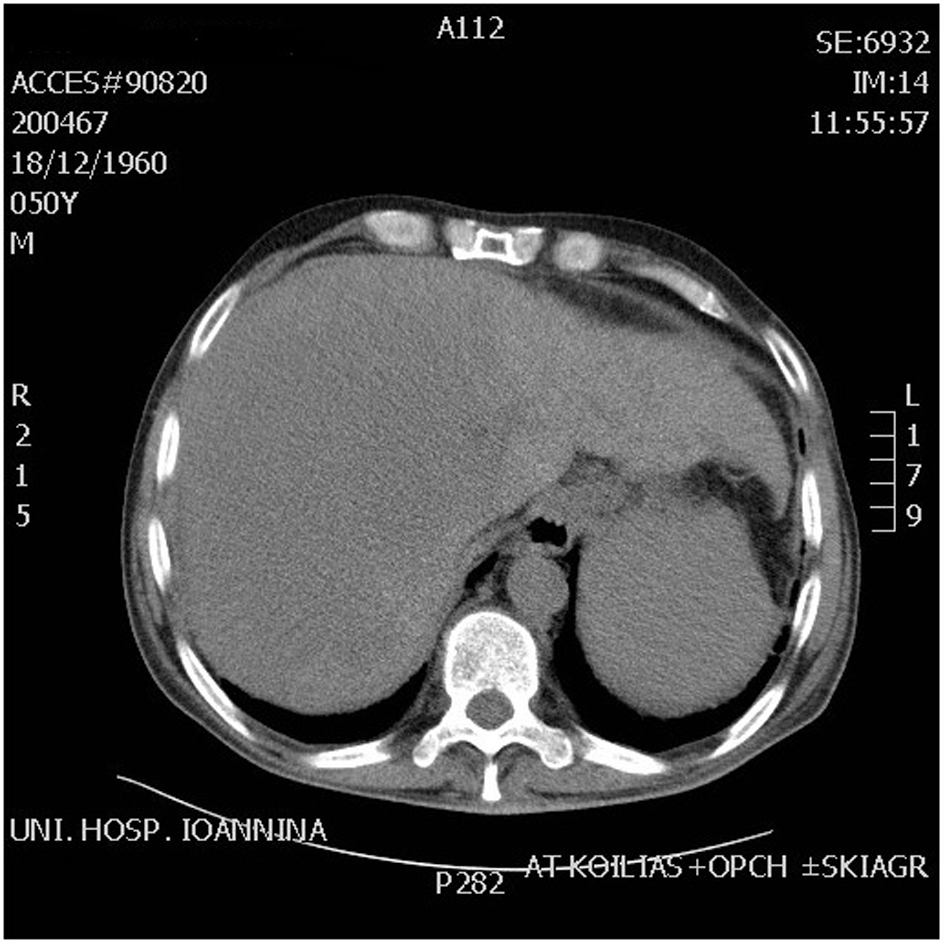

A 51-year-old patient with a history of active hepatitis-B viral infection, psoriatic arthritis, heavy alcohol and tobacco use, was referred to the Oncology Department having been recently diagnosed with metastatic HCC (stage IVB). A sizeable mass had been identified in the right liver lobe (Fig. 1) and bone metastases in the thoracic and lumbar vertebrae. The diagnosis was established by liver biopsy (Fig. 2) and a significantly elevated serum alpha-fetoprotein level (above 2,500 ng/mL reference values below 8 ng/mL). The biopsy was consistent with a poorly differentiated HCC and showed evidence of micronodular cirrhosis (Fig. 3). The patient was palliatively treated with sorafenib (multikinase inhibitor) 400 mg po bid.

![]() Click for large image | Figure 1. CT scan abdomen showing huge mass in the right lobe of liver. |

The patient received food-additives rich in carbohydrates, oral corticosteroids (dexamethasone 4 mg three times daily) and diazoxide (3 - 8 mg/kg/day orally divided in three doses therapy not really indicated as it works by reducing insulin secretion) with no apparent effect on control of hypoglycemia, before embarking on glucagon. He received IV glucagon at initial dose 0.06 mg/h, followed by 0.30 mg/h by continuous pump infusion, supplemented by carbohydrate-rich nutrition. Despite an initial good response lasting for 7 days, hypoglycemia episodes reappeared. A new abdominal CT scan highlighted the HCC lesion occupying the largest area of the right lobe (Fig. 1). Regional intra-arterial chemotherapy via the hepatic artery was administered by interventional radiology in the form of 700 mg fluorouracil and 700 mg gemcitabine together diluted with 100 cc normal saline, aiming for cytoreduction of IGF-producing malignant clone. Neither this method induced the desired effect. The patient’s clinical and laboratory deterioration was gradual (Child-Pugh C stage) over the third to sixth weeks of his hospitalization, resulting in coma and death on day 58 due to esophageal varices bleeding.